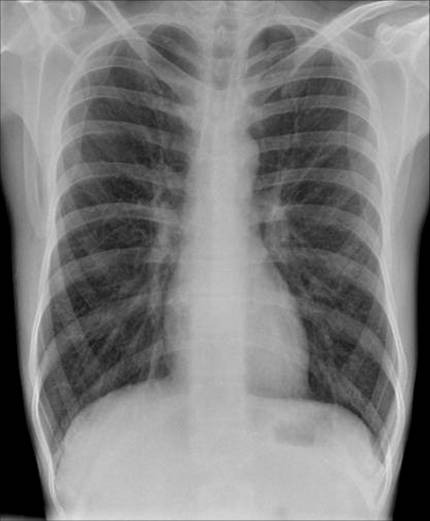

Typische Veränderungen im Thoraxröntgen (s. obiges Bild): Erhöhte Strahlentransparenz, abgeflachte Zwerchfellkuppeln, horizontal verlaufende Rippen, Erweiterung der Interkostalräume, Rarefizierung der Blutgefäße in der Peripherie